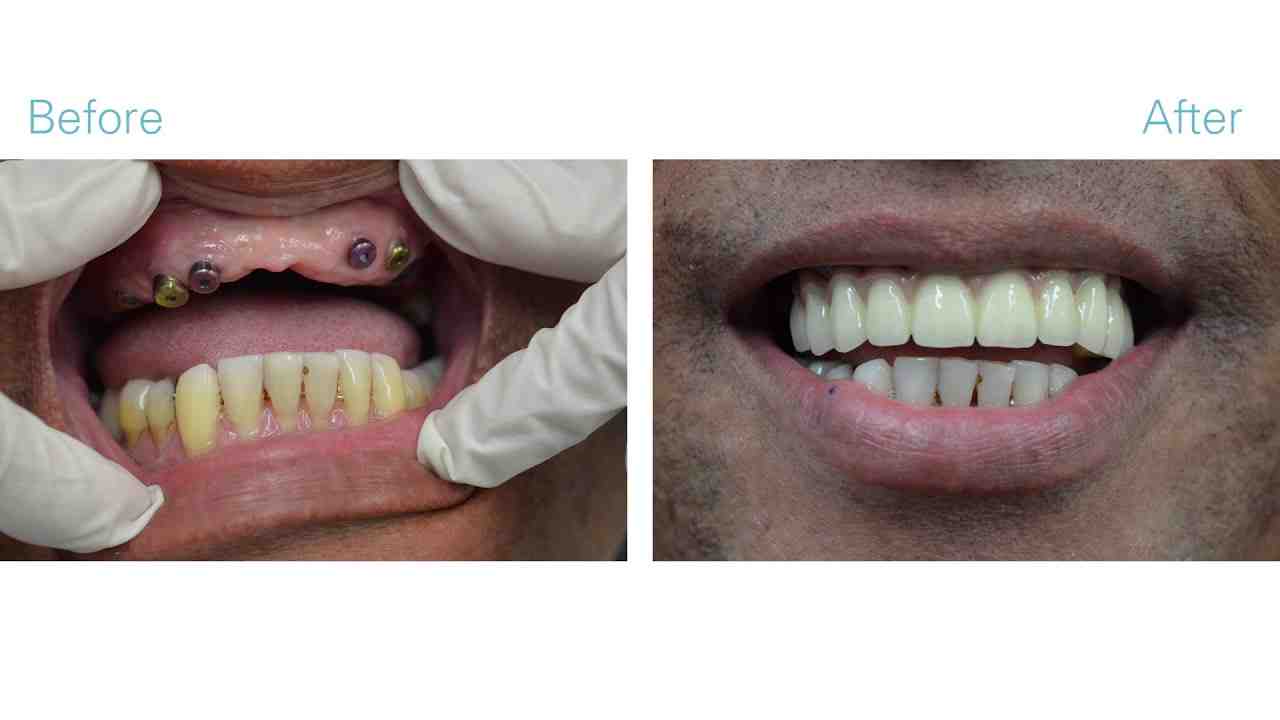

Can you get dental implants if you have bone loss?

When someone has problems with their teeth, doctors will often consider dental implants. Unfortunately, patients with severe bone loss in the jaw do not have enough bones for implants to remain securely embedded. On the same subject : Stem Cells Dental Implants. These patients are often told that they are not eligible for implants.

How many implants are needed for full mouth?

Which is better all on 4 or all on 6 dental implants?

The most obvious difference between all-in-4 and all-in-6 dental implants is the number of implants placed in the mouth. Some dentists believe that the all-in-6 dental treatment provides a stronger, more stable base for the prosthetic dental arch, resulting in a longer lasting and more pleasant smile.